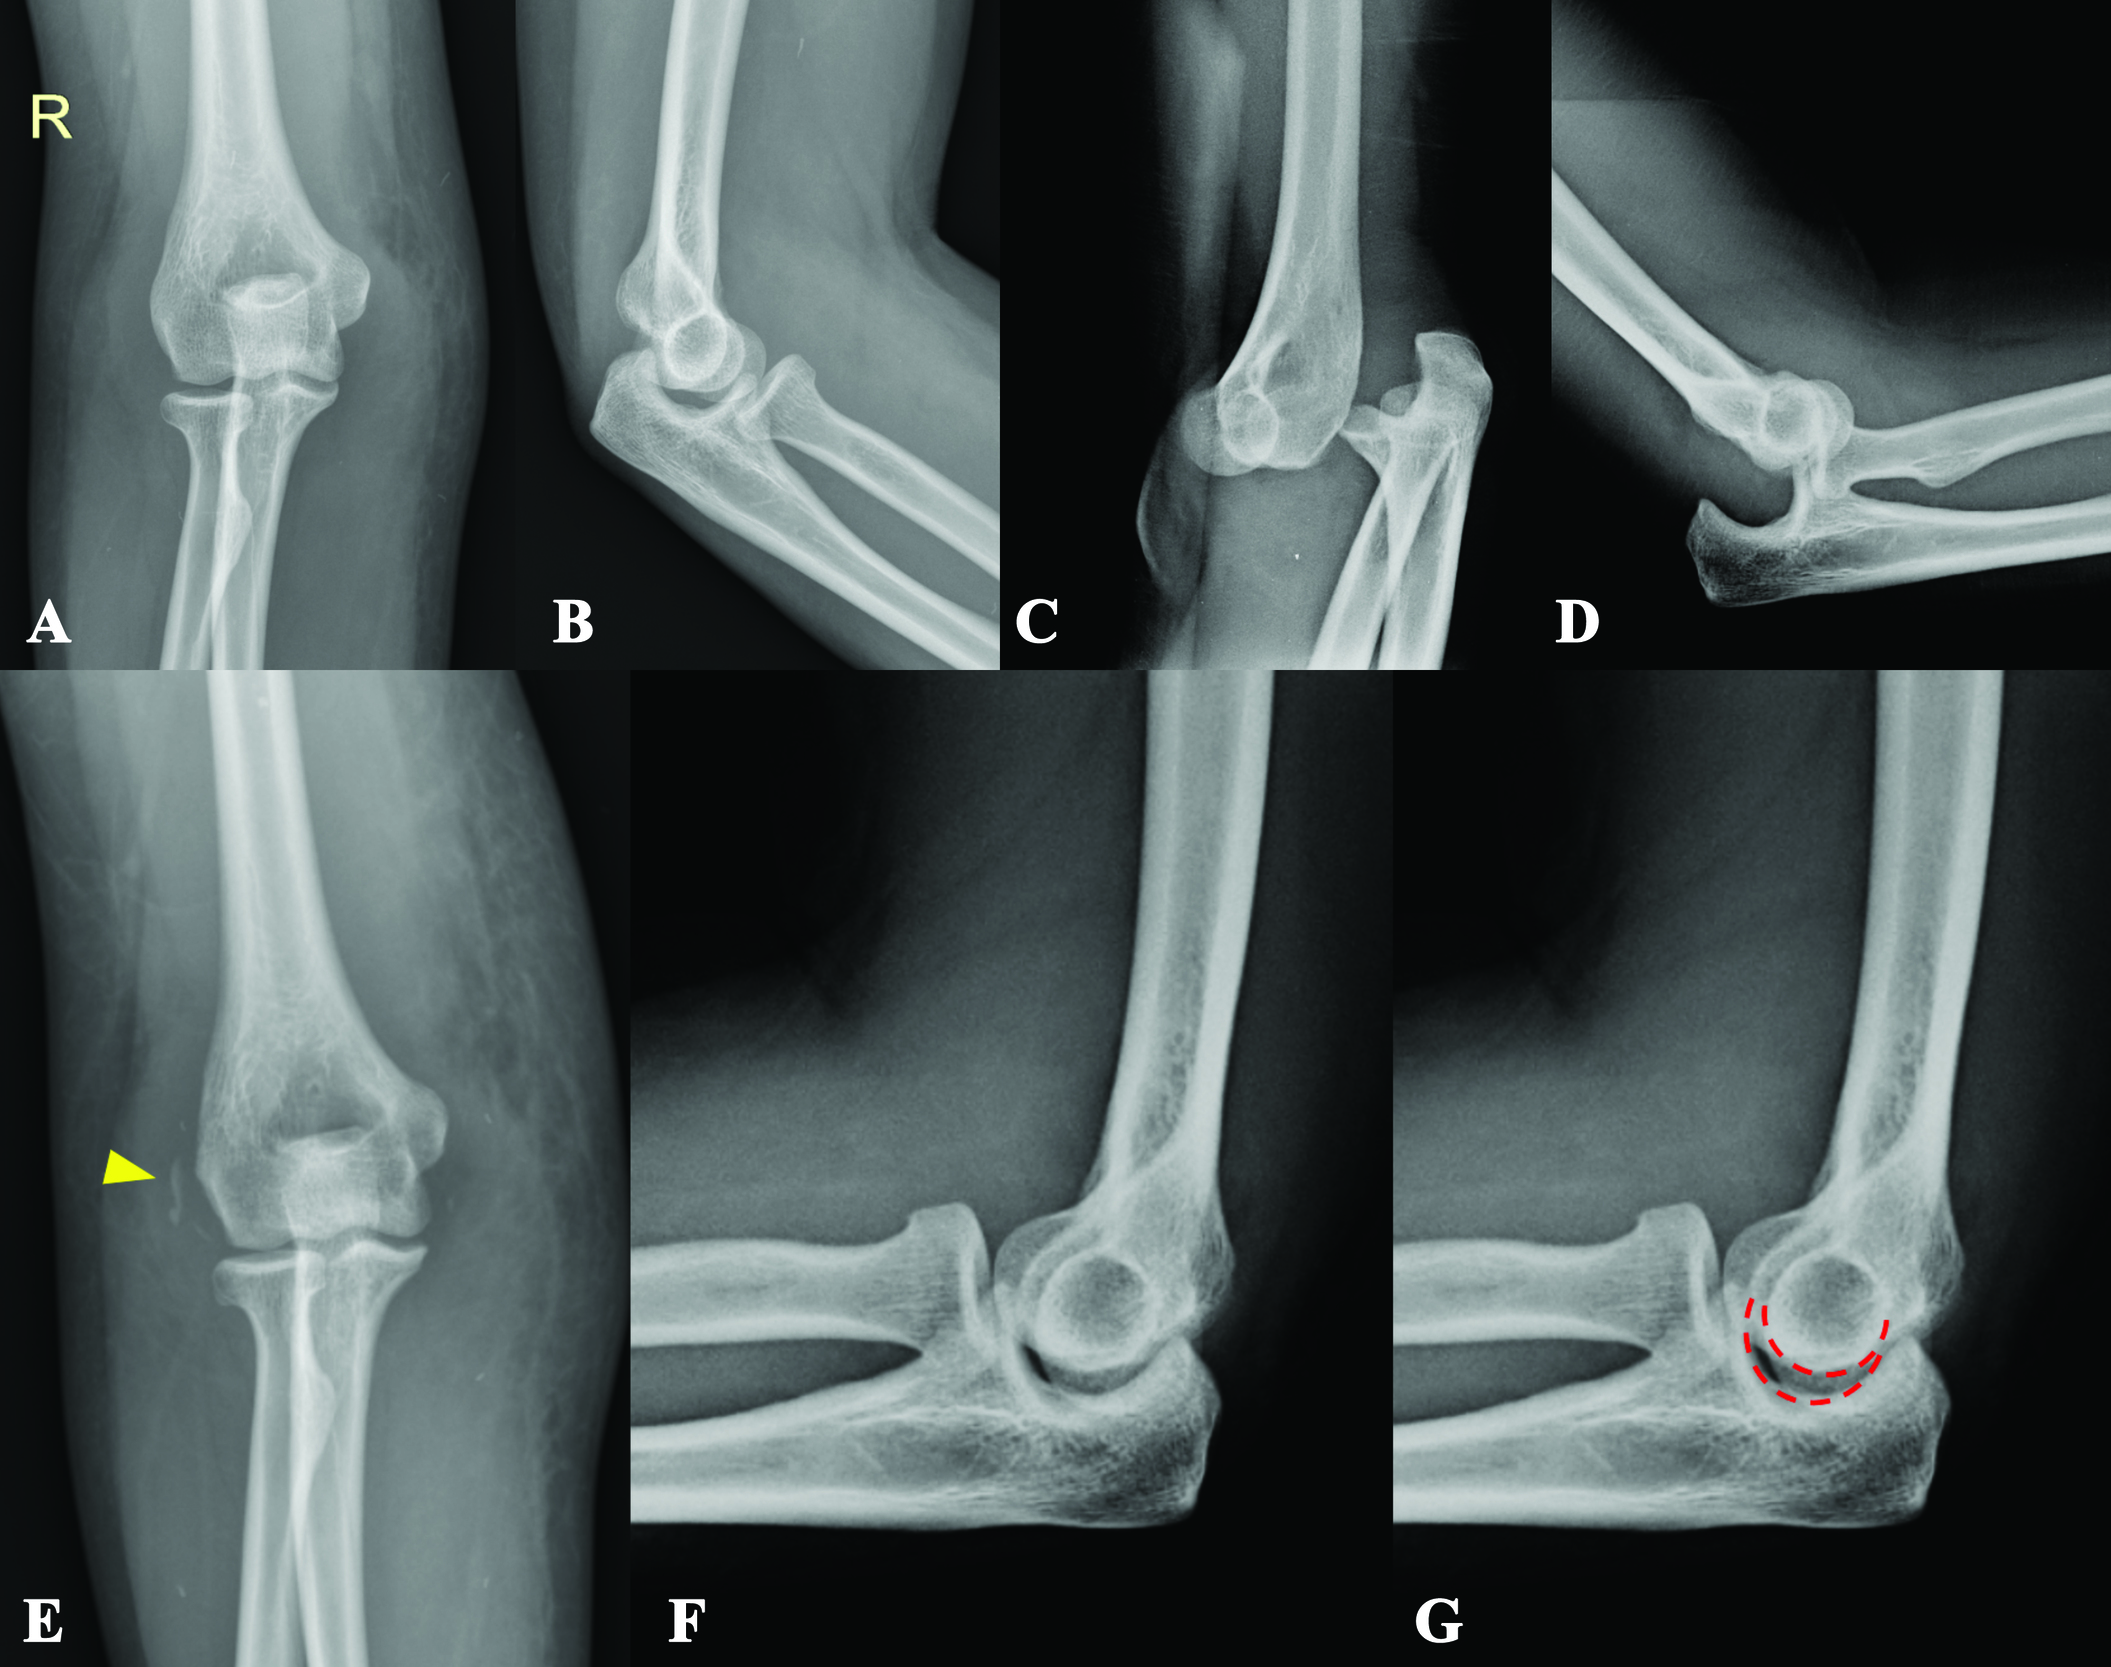

A 30-year-old female with a history of 5-year PLS presented with right elbow dislocation 30 minutes before arrival. Her status was generalized muscles weakness requiring wheelchair or gait-aids ambulation. Previously, she had a 3-month history of elbow injury. She recalled an apprehension of right elbow subluxation at that time, which was promptly self-reduced. Visiting her general orthopedist, the slab was applied for two weeks, and after removal, there was no clinical re-dislocation. Even so, she still experienced instability pain on her right elbow up until now. A drop sign was found from reviewing her plain films taken during the previous 3-month follow-up period (Fig. 1A-B).

Due to elbow discomfort and gait-aids-ambulatory status, she suffered another right elbow injury leading to recurrent dislocation at the current visit (Fig. 1C-D). After closed reduction under intra-articular lidocaine injection, a full range of motion with no re-dislocation upon full passive extension was noted. However, a more prominent joint incongruity and an avulsion fracture of the lateral epicondyle were observed (Fig. 1E-G). Subsequently, she was sent to consult with the Sports Upper Extremity unit. Upon evaluation and review of her previous injury history, she still had medial and lateral elbow pain, and acute-on-top-chronic elbow injury was impressed. Accordingly, with an avulsion fracture of the lateral collateral ligament and chronic instability pain, surgical intervention was indicated to restore ligament stability as the compensatory tension from her muscles was suspected to be inferior to that of the general population.2,3